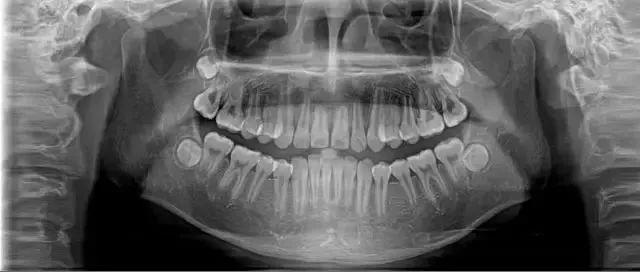

醫(yī)生經(jīng)過(guò)系統(tǒng)檢查后,確定這位年輕人出現(xiàn)全口多處牙齒的松動(dòng),診斷為侵襲性牙周炎。

經(jīng)過(guò)口腔醫(yī)院診斷,她患上了嚴(yán)重的牙周炎,醫(yī)生先后為其拔除了11顆牙齒,并種植了10顆牙齒。

28歲的小孟因刷牙時(shí)突然一顆門牙脫落,當(dāng)她到醫(yī)院就診時(shí),醫(yī)生告訴她上排牙已全部不能保留。

小孟的牙齒已經(jīng)出現(xiàn)了不同程度的松動(dòng),而導(dǎo)致她松動(dòng)至功能喪失的是嚴(yán)重的牙周炎。終只能將其牙拔去后,花費(fèi)十五六萬(wàn)元選擇種植牙。